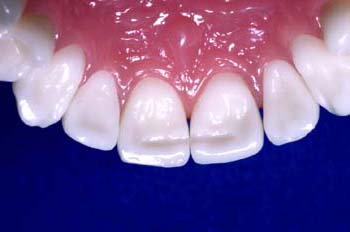

Estético y cómodo, el retenedor de Ribbond está finalizado.

Aplique una fina capa de composite adicional de modo que el retenedor quede nivelado con la estructura del diente circundante. El retenedor acabado “desaparece” dentro del composite sin ningún bulto

A diferencia de un alambre de metal, Ribbond ofrece una estética superior y no es visible.